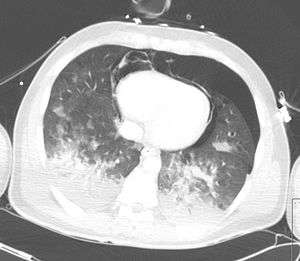

| A CT scan showing a pulmonary contusion (red arrow) accompanied by a rib fracture (blue arrow) | |

Computed tomography (CT scanning) is a more sensitive test for pulmonary contusion,[6][33] and it can identify abdominal, chest, or other injuries that accompany the contusion.[38] In one study, chest X-ray detected pulmonary contusions in 16.3% of people with serious blunt trauma, while CT detected them in 31.2% of the same people.[45] Unlike X-ray, CT scanning can detect the contusion almost immediately after the injury.[43] However, in both X-ray and CT a contusion may become more visible over the first 24–48 hours after trauma as bleeding and edema into lung tissues progress.[46] CT scanning also helps determine the size of a contusion, which is useful in determining whether a patient needs mechanical ventilation; a larger volume of contused lung on CT scan is associated with an increased likelihood that ventilation will be needed.[43] CT scans also help differentiate between contusion and pulmonary hematoma, which may be difficult to tell apart otherwise.[47] However, pulmonary contusions that are visible on CT but not chest X-ray are usually not severe enough to affect outcome or treatment.[37]